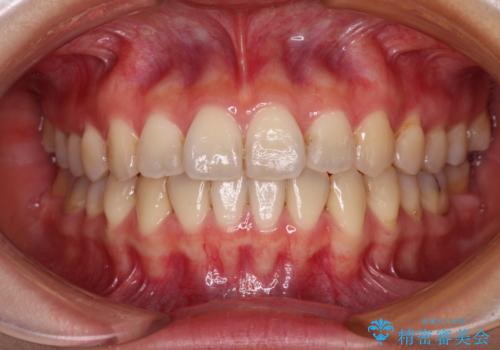

ディープバイトをインビザライン矯正で改善